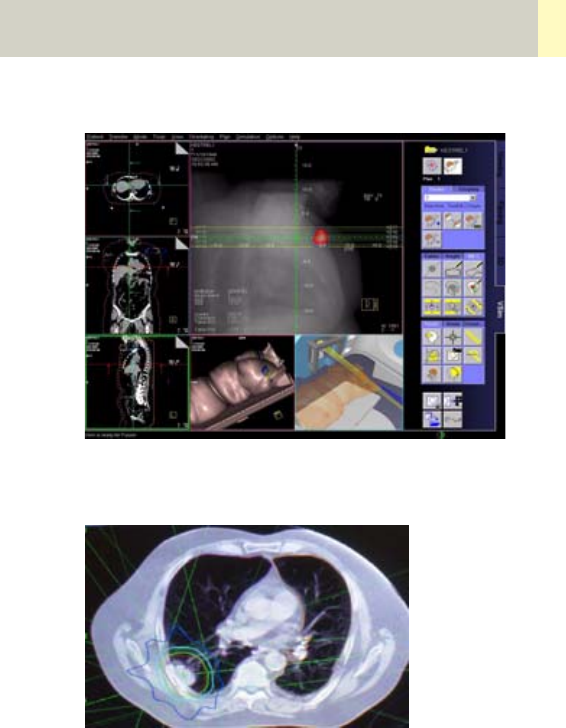

•Radiation Therapy Planning 462

•Workflow 468

•Scan Protocols 470

- Overview 470

- RT_Head 472

- RT_Thorax 474

- RT_Breast 476

- RT_Abdomen 478

- RT_Pelvis 480

- Additional Important Information 482